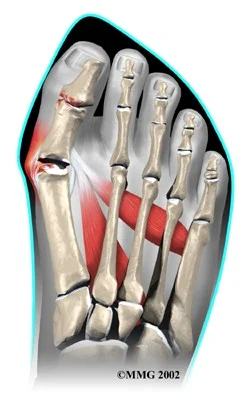

- Definition: lateral deviation of the great toe (hallux) and medial deviation of the first metatarsal

bunion

- Bunion may be (usually) inflamed / painful